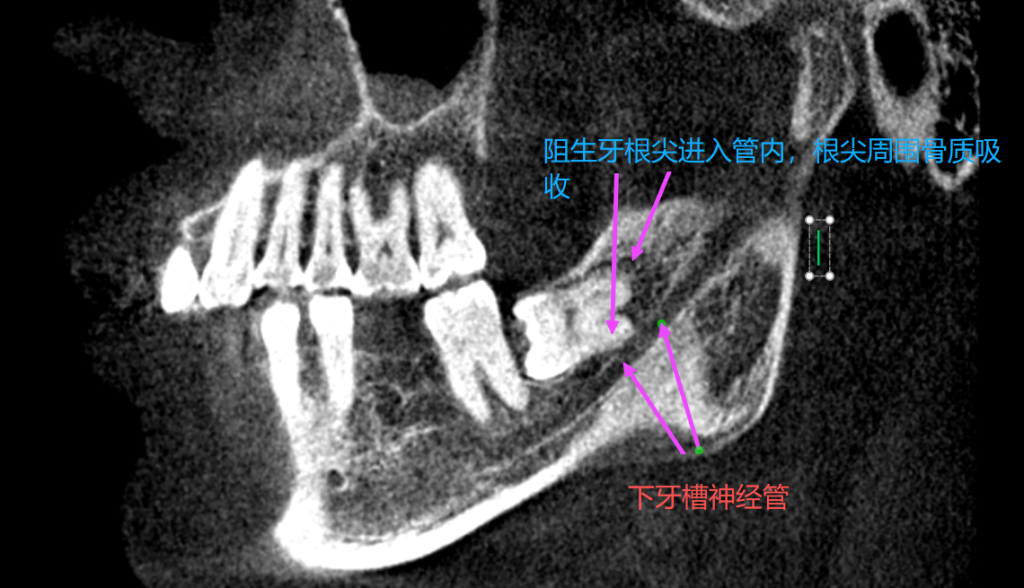

三叉神经为第五对脑神经,其第三支——下颌神经(V3)经卵圆孔出颅后分出下牙槽神经(inferior alveolar nerve, IAN),该神经经下颌孔进入下颌管,沿途支配下颌牙齿、牙龈及下唇等区域。下牙槽神经走行于下颌骨内的神经管中,与第三磨牙(智齿)根尖解剖关系密切,二者之间的最短距离可小于1mm,甚至存在根尖穿入神经管的情况。

影像学检查在诊断中具有重要价值: - 根尖片或全景片可初步判断牙根与神经管关系;

- CBCT(锥形束CT)可三维重建神经管与牙根的空间位置,评估压迫程度与风险

微血管减压术后,三叉神经痛复发。行口腔CT检查,发现阻生齿导致三叉神经痛。